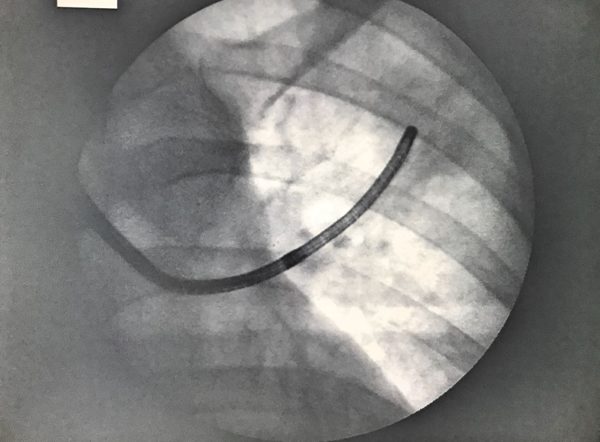

Diagnostica sempre più all’avanguardia all’ospedale La Maddalena di Palermo. Un broncoscopio ultrasottile di ultima generazione è entrato a far parte delle apparecchiature sanitarie usate nel dipartimento oncologico, prima struttura in Italia a dotarsi di questo nuovo strumento diagnostico. Si tratta di un dispositivo che, lavorando in sinergia con le sonde ecografiche miniaturizzate e con i sistemi di navigazione, è in grado di scandagliare i bronchi fino alle ramificazioni più sottili, difficili da raggiungere con altri dispositivi.

Il nuovo broncoscopio si rivela utile nella diagnosi avanzata del tumore al polmone e si va ad integrare con le tecniche chirurgiche mininvasive introdotte già da qualche anno nel dipartimento oncologico palermitano. Oggi nell’80 per cento dei casi, i pazienti vengono operati al polmone con chirurgia toracoscopica, ovvero attraverso metodologie mininvasive.